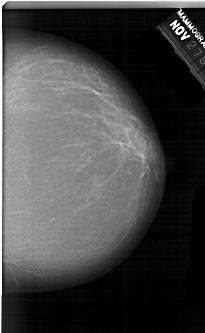

A_1519_1.RIGHT_CC

RIGHT_MLO LINES 5956 PIXELS_PER_LINE 3781 BITS_PER_PIXEL 12 RESOLUTION 43.5 NON_OVERLAY